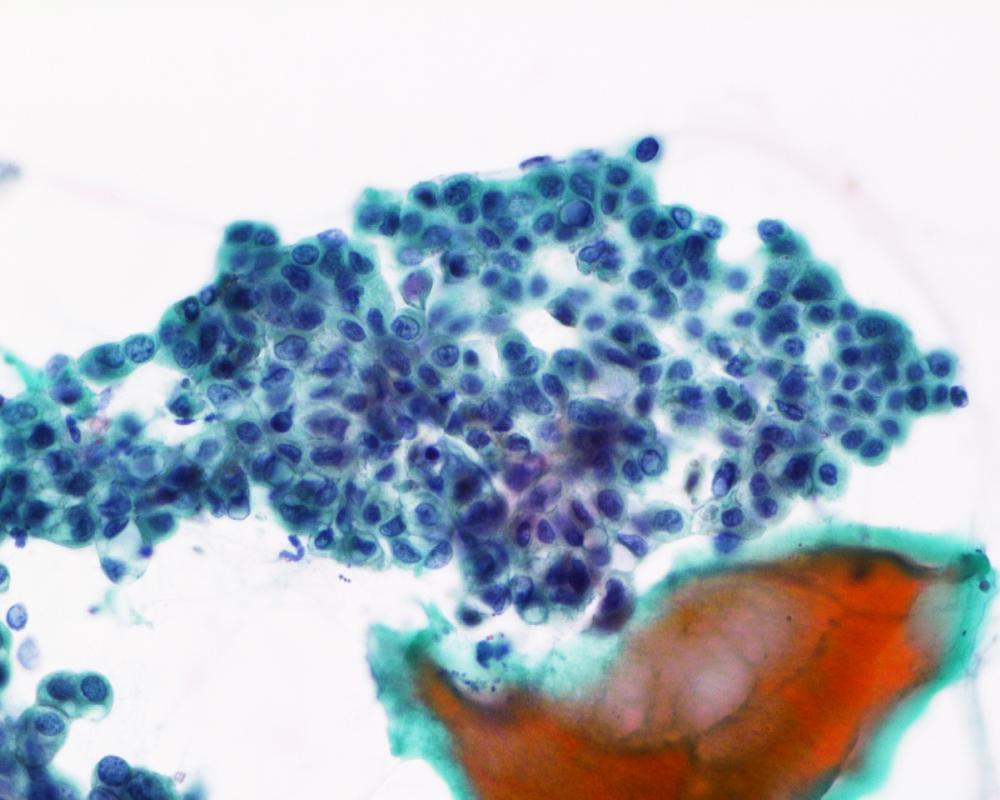

第38回日本臨床細胞学会九州連合会学会(熊本)スライドカンファレンス症例1

種別:婦人科

出題:仲田 典弘 中頭病院病理診断科

| 年齢 | 70代 | 性別 | 女性 |

| 採取部位 | 右卵巣 | 採取方法 | 捺印 |

既往歴:右乳癌(7年前)、右卵管妊娠(40年前)。

現病歴:半年前から腹部膨満感あり受診。造影CTで嚢胞性卵巣腫瘍が疑われ手術となった。

| 正解 | 5.ブレンナー腫瘍 |

▼選択肢及び投票結果

| 1.奇形腫 | 10件 | (9.6%) | |

| 2.明細胞癌 | 34件 | (32.7%) | |

| 3.類内膜癌 | 7件 | (6.7%) | |

| 4.顆粒膜細胞腫 | 12件 | (11.5%) | |

| 5.ブレンナー腫瘍 | 41件 | (39.4%) | |

| 投票総数 | 104件 | (100%) |